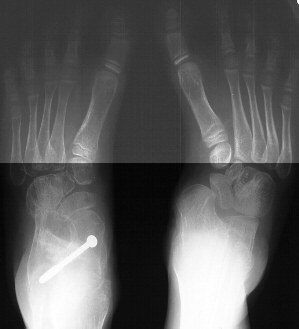

Radiographs reveal the following deformities:

- hindfoot valgus with AP talocalcaneal angle of > 35 degrees

- lateral subluxation/dislocation of the navicular from the talar head

- adduction of the metatarsals with the talus- 1st metatarsal angle to

be divergent medially

- increased lateral talocalcaneal angle with talus plantarflexed on calcaneus